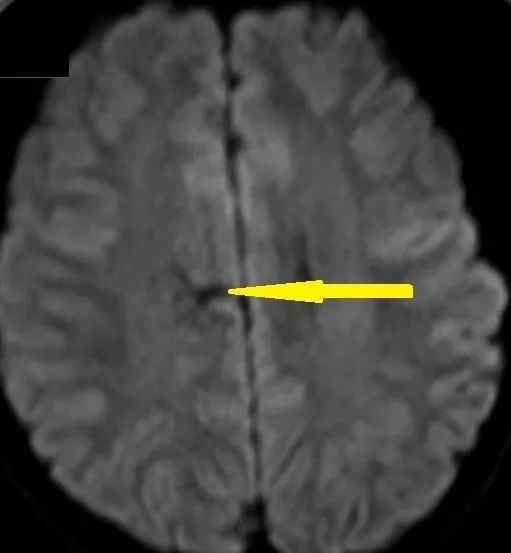

男, 41,头痛头晕3个月。

答案:结核性肉芽肿

又是非常丰富的影像学资料。乍一看又像是个大瘤子,鉴别脱髓鞘假瘤。

灌注成像,病灶这一块有高有低,像是病灶核心有点高灌注,水肿的地方低灌注。波谱也只能提示神经元受损,有一点脂质波,没有很强的特异性。DWI高,似乎支持淋巴瘤。没想到结果出来却是结核性肉芽肿。

复习一下脑结核性肉芽肿(也称结核瘤)的影像特点:

圆形或分叶样结节,CT呈等密度、稍高密度或混杂密度。核磁上T1等信号或低信号,T2新鲜病灶可呈稍高信号,老病灶常呈低信号。

中心干酪样坏死的信号变化取决于坏死物内水的含量及蛋白质、脂质浓度,可呈长T1、长 T2,等T1、长T2信号,等T1、短T2信号改变。

可有伴中至重度水肿。增强扫描可呈结节样或环形强化。CT上可表现为中心钙化、环以周围增强,称为靶征。

一般总感觉结核性肉芽肿似乎比较小,没想到也遇到这种长的比较大和其他肿瘤相似的。今后要注意鉴别。